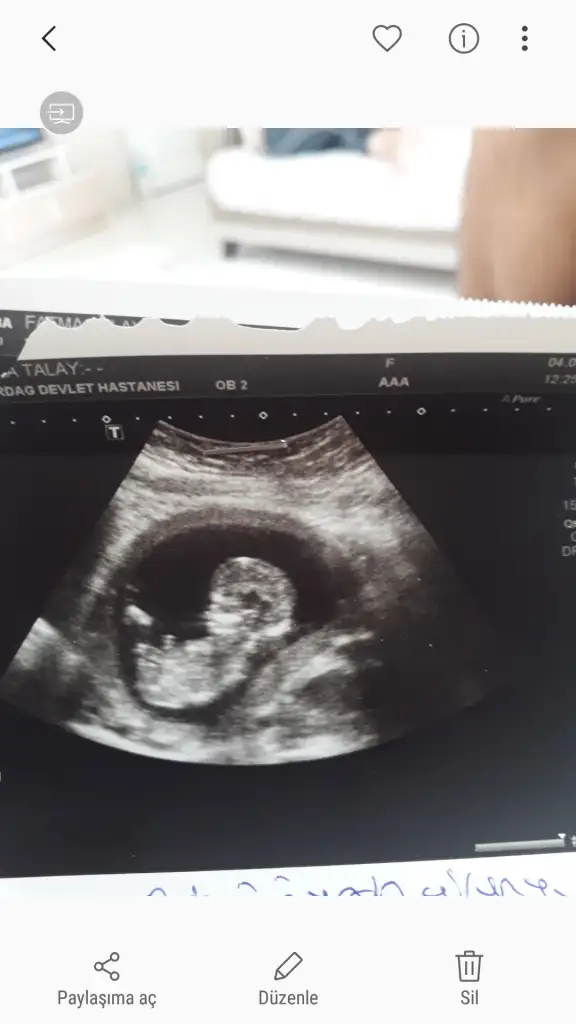

Bugün ikili test için gittiğim Dr. da kız dedi dünde erkektiKafamız cok karıştı çıkıntı düz çünkü dedi o da ama bu kadar büyük çıkıntı okuyor mu sizce ?

Usg yaniltmiyorsa ki yan donmus sanki kiz gibi bu bebisteEki Görüntüle 2307207

Arkadaşlar bebegimin cinsiyetine bakar mısınız 11+6 haftalık 9. Haftalıkken atmıştım ama net değildi şimdi atmak istedim